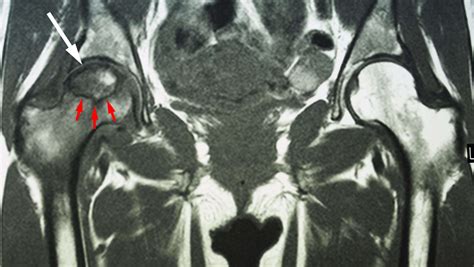

Clinicians typically categorize Avn disease hip into four distinct stages based on imaging techniques like MRI and X-rays. Identifying the stage is paramount because treatment options vary drastically depending on how much of the femoral head is affected.

Stage I Normal X-rays, but visible changes on MRI. Minimal or intermittent hip pain.

Stage II Sclerosis or osteopenia visible on X-ray. Increased pain with weight-bearing activities.

Stage III The "crescent sign" appears, indicating subchondral collapse. Constant ache, limited range of motion.

Stage IV Degenerative changes and joint surface destruction. Severe pain and significant mobility loss.

Early detection is the single most important factor in saving the natural hip joint. Because symptoms are often referred to the knee or groin area, many patients are misdiagnosed initially. If your physician suspects Avn disease hip, they will likely utilize a combination of clinical examinations and advanced imaging. An MRI is considered the “gold standard” because it can detect the death of bone cells months before any changes appear on a standard X-ray.

• MRI Imaging: Detecting the lack of blood flow or early bone marrow changes.